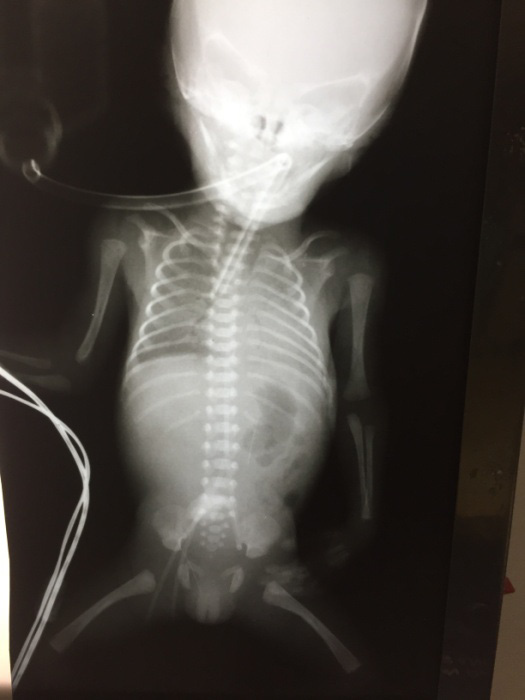

Administrada primeira dose de surfactante com aproximadamente 1h30min de vida. Ao exame apresenta-se estável, tolerando reduzir parâmetros, mas apresentando ausculta respiratória reduzida à esquerda.

A figura a seguir apresenta o raio X de tórax do paciente.

De acordo com o RX apresentado, são diagnósticos que justificam a ausculta respiratória diminuída à esquerda: